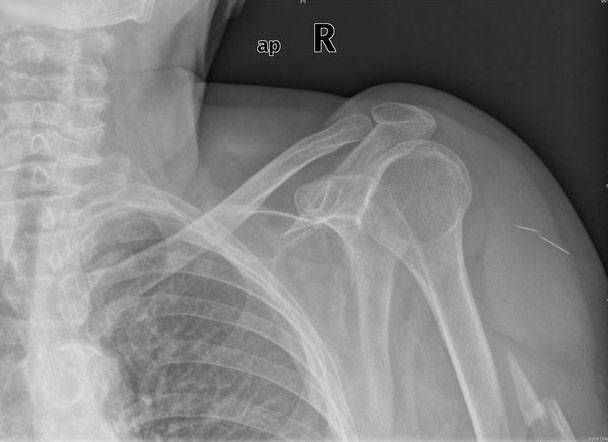

Fractura impactada de húmero .

Fractura de húmero, intensa desviación de fragmentos